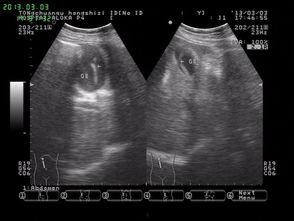

接下来,让我们一起来了解一下蛔虫手术的具体过程。首先,医生会为患者进行全身麻醉,确保患者在手术过程中不会感到疼痛。医生会在患者的腹部切开一个小口,找到寄生着蛔虫的肠道。接着,医生会小心翼翼地将蛔虫从肠道中取出,最后缝合伤口。